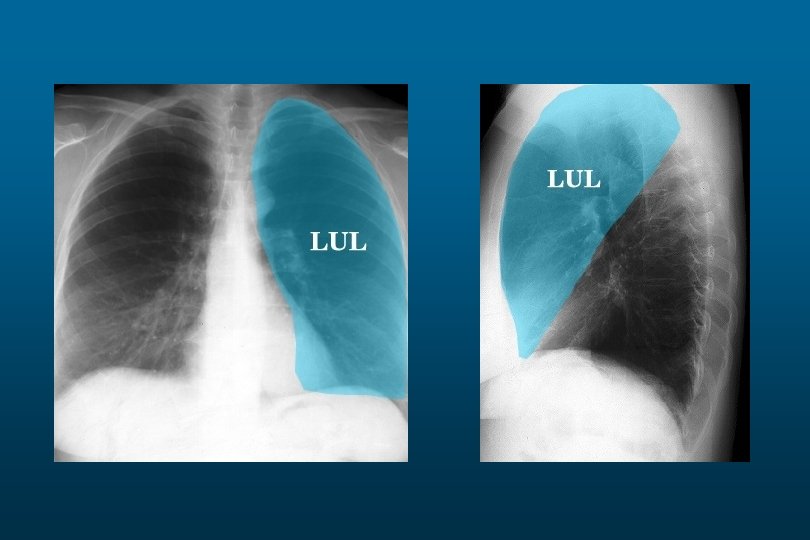

Left Lower Lobe Pneumonia

Left sided massive pneumonia